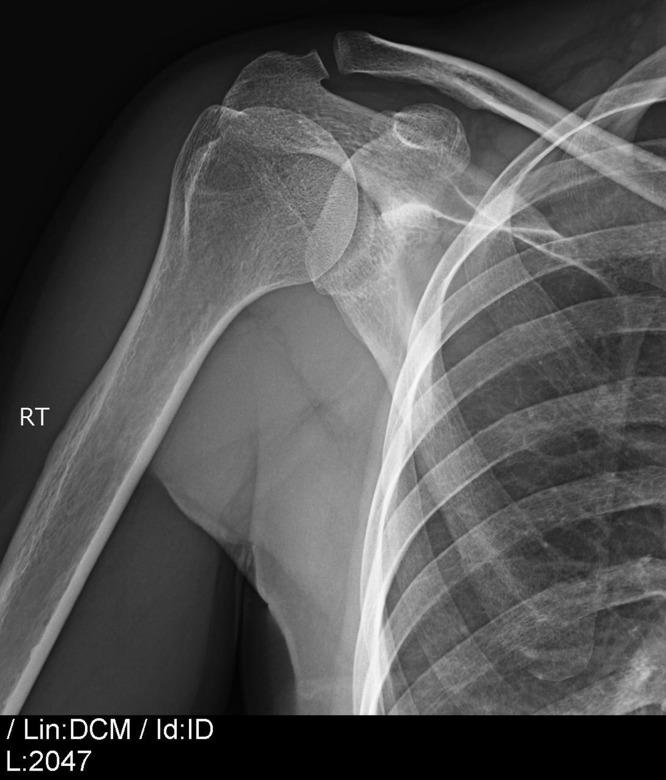

钙化沉积物针刺联合体外冲击波疗法(ESWT):一种针对冈上肌钙化性肌腱炎的拟议治疗方法。

Calcific deposit needling in combination with extracorporeal shock wave therapy (ESWT): A proposed treatment for supraspinatus calcified tendinopathy.

Calcified tendinopathy of the rotator cuff is one of the most common conditions concerning the shoulder pathology. It is characterized by a reactive calcification that affects the tendons being part of the rotator cuff. The reported prevalence varies from 2.7% to 22%. Most of the patients can be treated effectively with non-operative measures such as anti-inflammatory drugs, subacromial injection of steroid, physiotherapy, extracorporeal shock wave therapy (ESWT) and needle aspiration irrigation. Results of a treatment combining some of these methods have not been reported.

Sixty-six consecutive patients (68 shoulders) were treated for calcified tendinitis of supraspinatus, which was diagnosed clinically and radiologically, with needle drilling using xylocaine under ultrasound guidance. After the drilling the patient followed a physiotherapy protocol with ESWT which included five visits within a month. After the end of the physiotherapy, the patients were evaluated clinically and radiologically. The Visual Analogue Scale (VAS) for pain and the Disabilities of the Arm, Shoulder, and Hand (DASH) score were measured before and after the end of the therapy.

All the patients showed clinical improvement of the symptoms at the follow-up. The mean VAS score showed improvement from 8.1 to 3.3 whereas the mean DASH score was 27 and after the end of the therapy 5. Radiologically all but one calcific deposits were disappeared.

The ultrasound-guided drilling of the calcific deposit using xylocaine, in combination with physiotherapy using ESWT provides a reliable alternative treatment for the calcific tendinitis of the supraspinatus.